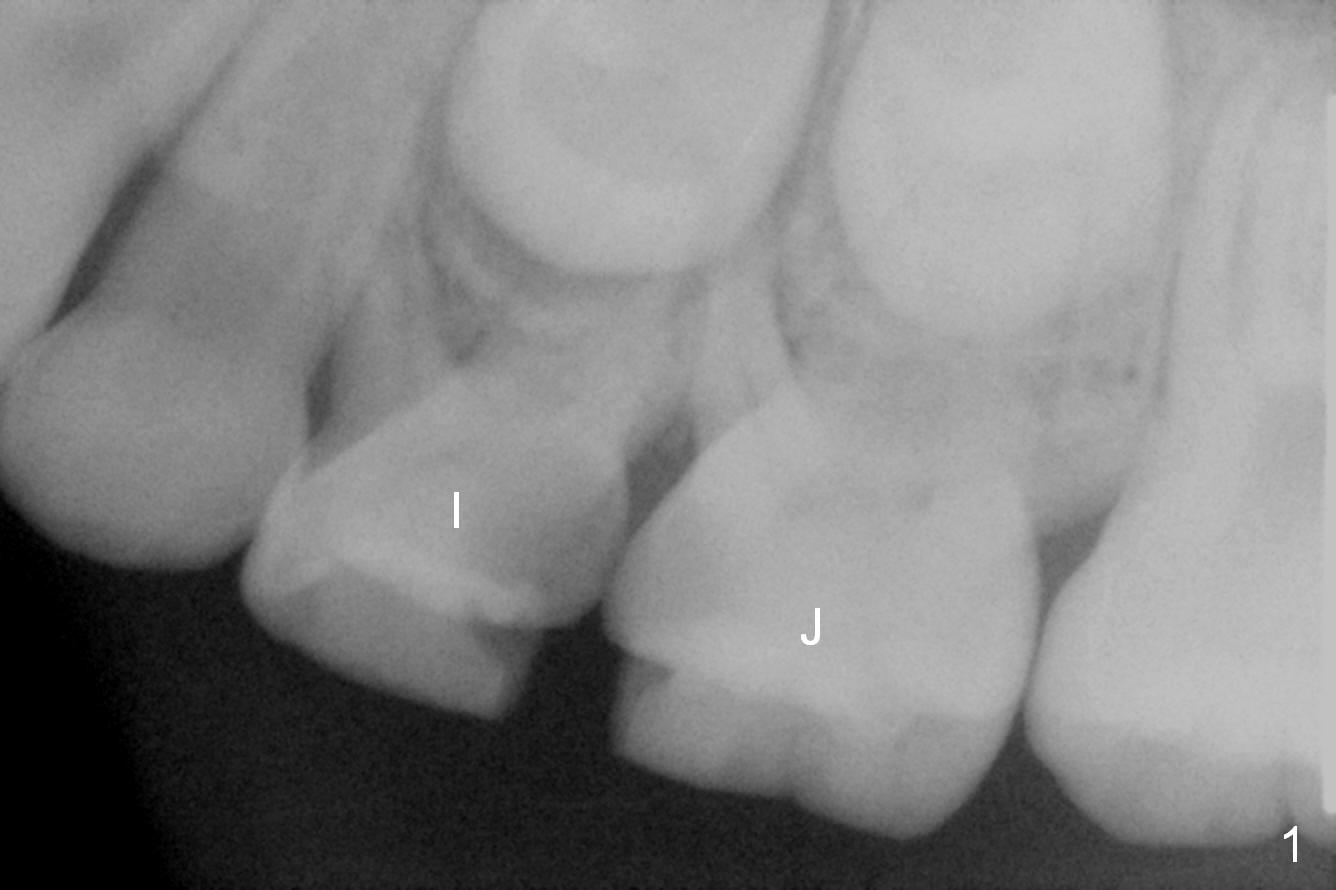

A 11-year-old girl returned to clinic, two years after last visit (Fig.1). The carious teeth I and J were extracted and space maintenance was fabricated in another office later. The latter dislodged without recementation.